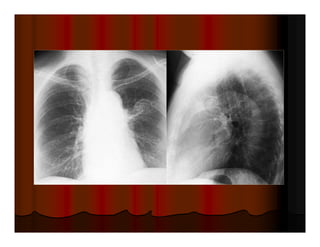

Cavitating squamous cell carcinoma: hang lệch tâm, thành hang dày

Female: cavitary lesions, metastatic squamous cell carcinoma (cervix).

Mỗi hang thường có một banh nấm

Mukesh G. Harisinghani, MD et al. Tuberculosis from Head to Toe. Radiographics.

2000;20:449-470.